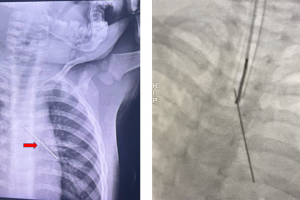

Vừa qua, bệnh viện Nhi Đồng Thành Phố tiếp nhận một trường hợp trẻ N. H. P. 14 tuổi, nam, cân nặng 63kg, ngụ ở Phường Thanh Đức, Vĩnh Long. Khai thác bệnh sử...